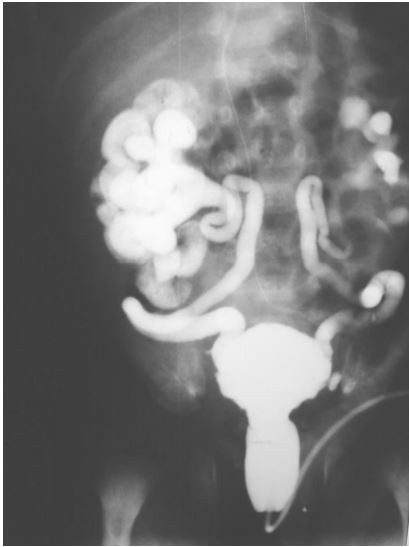

Lactente masculino apresenta infecção urinária de repetição e sepse. Tem diagnóstico pré-natal de hidronefrose bilateral. Realizou este exame radiológico contrastado.

Pode-se afirmar que:

Este exame é uma urografia excretora.

O diagnóstico radiológico é de bexiga neurogênica com refluxo.

Trata-se de um refluxo vesicoureteral de baixo grau.

O quadro radiológico é compatível com válvula de uretra posterior.